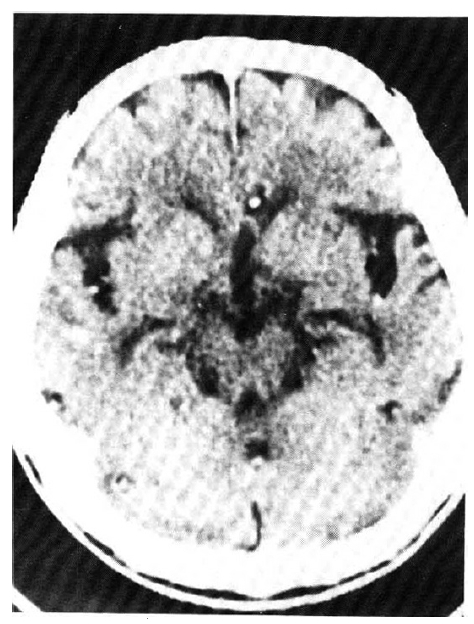

An X-ray film of the chest showed multiple nodular densities throughout both lower lung fields (Fig. 1). A computed tomographic scan of the brain and chest revealed multiple nodular and small calcified densities (Fig. 3, 4).

A biopsy of a subcutaneous nodule was done on the 4th hospital day, and upon microscopic examination, a bladder worm (Fig. 5)—its hooks (Fig. 6) and parenchymatous portion with spinal canal and separated bladder of the cysticercus (Fig. 7)—was observed. On the 12 th hospital day, the presence of cysticercus was confirmed by an open lung biopsy (Fig. 8).